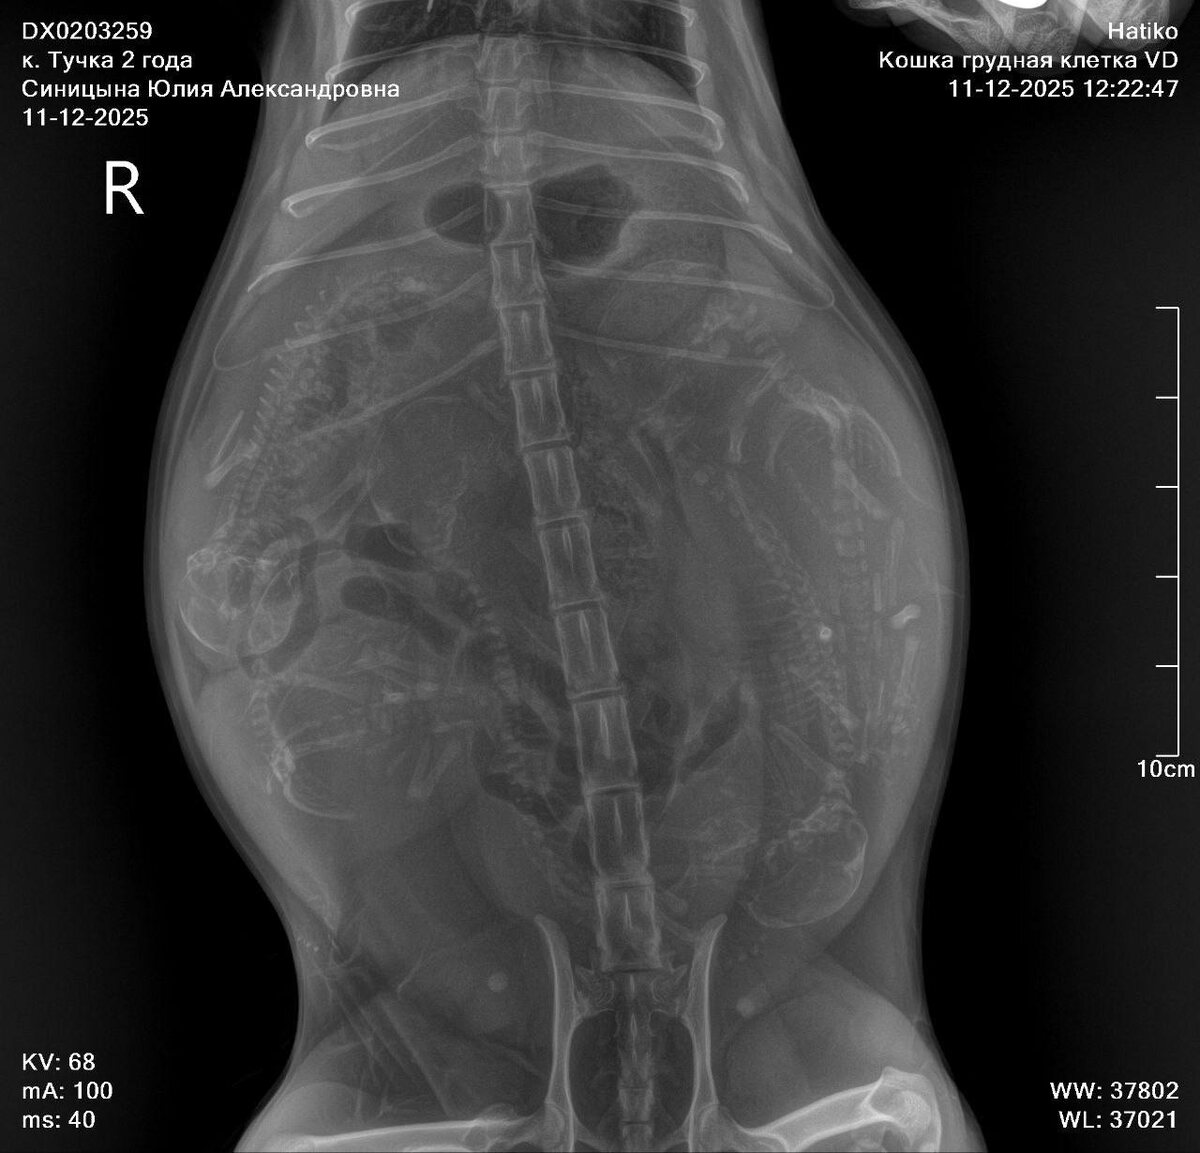

Посчитаем котят #Тучка вместе

Посчитаем котят #Тучка вместе? )))